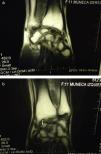

Carpal X-rays showed bilateral scaphoid bone rarefaction, with marked sclerosis and severe degenerative signs (Fig. 1), this lesion was confirmed on magnetic resonance imaging (MRI). These findings were compatible with bilateral osteonecrosis (ON), leading to the diagnosis of bilateral, idiopathic Preiser's disease, upon not finding any associated pathology (Fig. 2A and B).

(A) Coronal MRI T1WI (TR 432, TE 26). Right scaphoid fracture with necrosis of the proximal fragment, markedly hypointense (arrow), with chronic degenerative changes due to instability. (B) Coronal MRI T1WI (TR 432, TE 26). Fracture of the left scaphoid bone without consolidation or changes in the signal pattern of the proximal fragment, with degenerative changes due to instability (arrow).